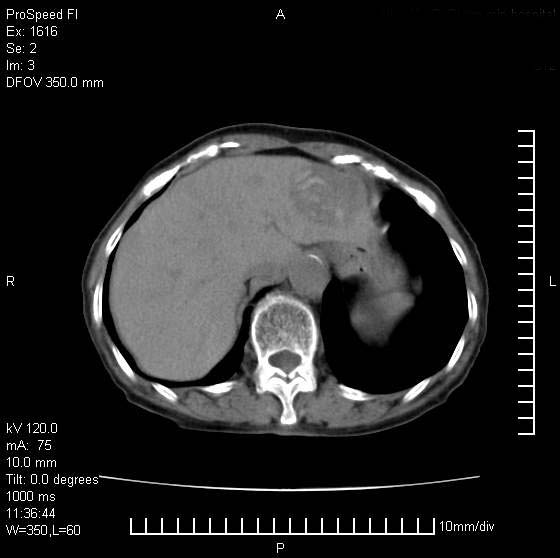

患者无明显临床症状,肝左叶发现一个圆形密度不均的低密度灶,边界较清楚,大小37x45mm,ct值35-70,患者犹豫做增强,如有增强片,我再发上,现先请各位老师会诊.

左肝外叶可见较大圆形低密度影,病灶可见较光整清晰边界,病灶内可见多量条状稍高密度影,右肝前叶亦可见圆形结节状低密度影,边界清晰,密度均匀,考虑1肝多发囊肿,左肝囊肿内出血2肝包虫病3左巨块型肝癌出血合并右肝转移或合并右肝囊肿

左肝外叶可见较大圆形低密度影,病灶可见较光整清晰边界,病灶内可见多量条状稍高密度影

考虑:肝包虫病

肝左叶类圆形低密度影,内可见略高密度影,边界清晰周边可见环形低密度带,考虑肝腺瘤可能,建议增强扫描除外肝血管瘤与肝癌

条带壮高密度影好象胃窦粘膜?考虑:1-慢性肝脓肿.2-胃窦溶积效应

病灶内高密度影,从ct值上看是血的密度还是某种纤维组织呢?似乎有内缘有包膜,肝脏各叶比例略失调,脾脏有点大.

hcc(巨块型)伴出血,突破肝包膜,肝胃韧带内,腹主动脉旁淋巴结转移;肝硬化

肝左叶不均匀占位,内有斑片状高密度出血灶,内侧缘似有假包膜,腹主动脉周围及肝门区结构紊乱,似有增大淋巴结,考虑:肝左叶hcc并淋巴结转移。建议增强扫描除外其他。